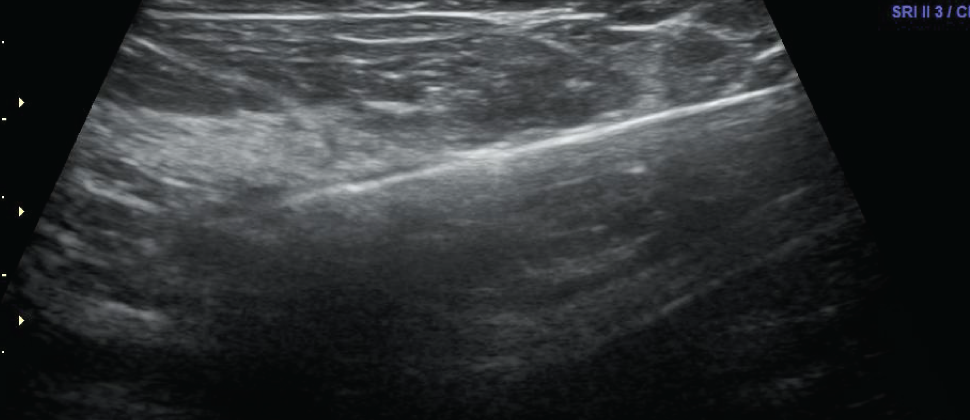

Una biopsia guiada por ultrasonido utiliza ondas sonoras para ayudar a localizar un bulto o anormalidad y extraer una muestra de tejido para examinarla bajo microscopio. Es menos invasiva que la biopsia quirúrgica, deja poco o nada de cicatriz, y no requiere de la exposición a la radiación ionizante.

La biopsia guiada por imágenes se realiza tomando muestras de una anomalía bajo alguna forma de guía, como ultrasonido, resonancia magnética o guía mamográfica.

Las imágenes por ultrasonido se utilizan para ayudar a guiar los instrumentos del radiólogo hasta el sitio del crecimiento anormal.